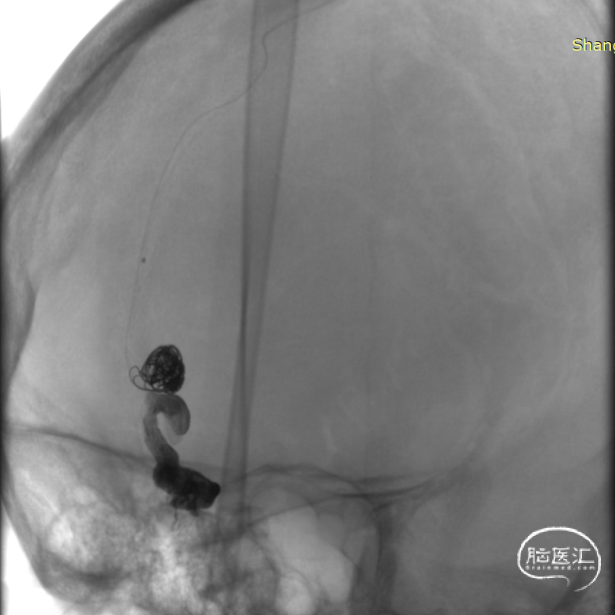

125cm Tethys®中间导引导管利用其远端柔软性,经长鞘高到位后,稳定支撑通路系统。

Echelon微导管经DCwire™微导丝,经过近端扭控,远端克服刁钻“回转弯”后引导微导管顺利进入近端静脉球。后马拉松微导管到达近动脉瘘口。

DCwire™微导丝配合Echelon微导管、通过优秀的扭控到位性及输送性,为微导管顺利到位提供保障。通过Echelon微导管首先稳定栓塞近端静脉球。

近端静脉球弹簧圈致密栓塞后,经马拉松微导管注入Onyx18。

顺利“安全”地注入Onyx18,瘘口完全栓塞,造影提示一期治愈,正常皮层引流静脉得以保留。

术后即刻造影见DAVF完全栓塞。